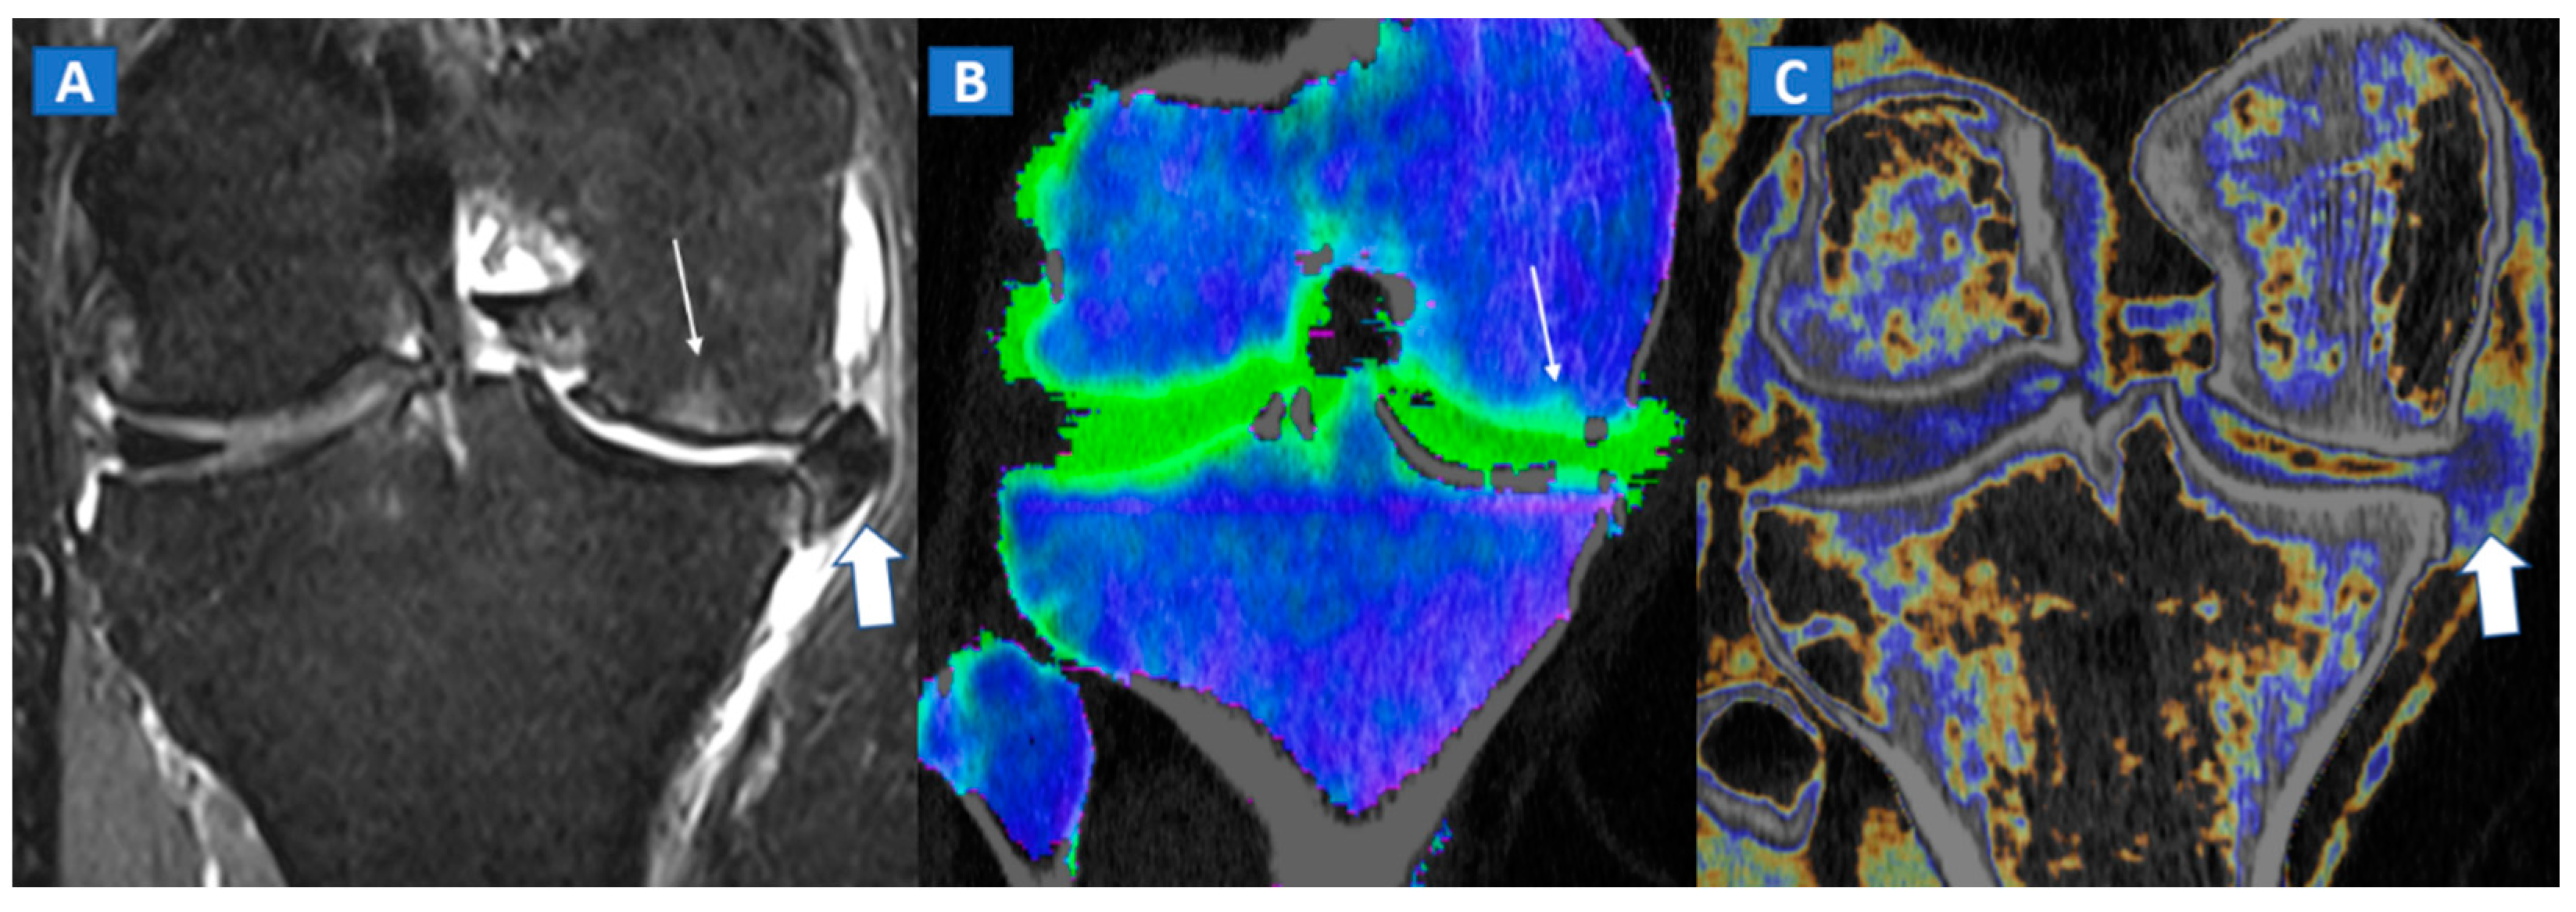

6. Non-Traumatic Osteochondral Lesions